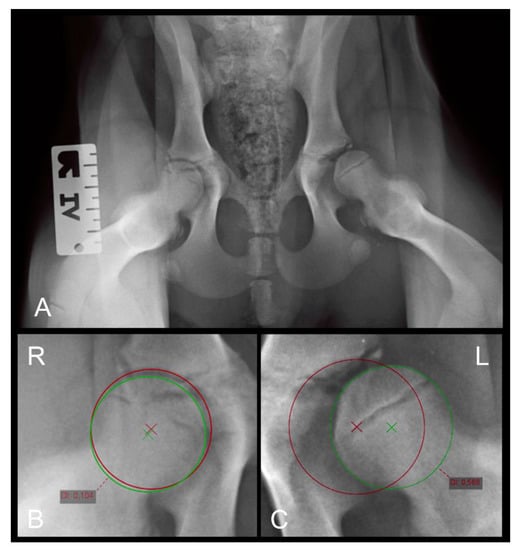

The NA presents information about the location of the center of the femoral head relative to the craniolateral acetabular margin and is reported to be ≥105° in normal hips in most breeds [1]. Smaller NA values usually represent subluxated/luxated femoral heads. The measurement of the NA is based on the measurement of the angle between the straight line connecting the centers of the contralateral femoral heads in ventrodorsal radiographs and the line connecting the center of the femoral head at each side with the intersection of the dorsal rim and craniolateral border of the acetabulum. The measurement of the NA is shown in Figure 1.

The LCFH was evaluated according to its position relative to the dorsal acetabular rim (medial, on, or lateral). The results were categorized as medial to DAR, superimposing DAR, 0–2 mm lateral to DAR, and more than 2 mm lateral to DAR (Figure 1).

Figure 1. (A) Extended FCI conform ventrodorsal radiograph of a four-month-old Rottweiler with what were assumed to be normal hip joints. Note the transitional lumbosacral vertebrae (type III). Right is always to the left of the images. (B) Magnification of (A), focusing on the hip joints: demonstration of Norberg angle measurement. (C) Section of a VD radiograph in another four-month-old Rottweiler puppy with obvious laxity of both hip joints, more severe on the left side. The femoral head center is positioned on, or barely medial to, the dorsal acetabular rim in (B) and definitely lateral to the DAR in (C) bilaterally. (D) Magnification of (C), demonstrating the actual distance of the femoral head center from the DAR.

Figure 2. (A) Distraction view VD radiograph of a four-month-old Rottweiler (same dog as in Figure 1A,B). (B) A magnification of the right and (C) a magnification of the left hip joint demonstrating the distraction index measurements. Note the laxity in the left joint which was not obvious in the extended view.